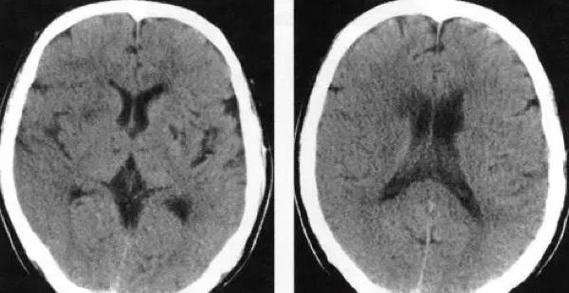

脑出血(出血性脑卒中):

- CT表现:这是CT最擅长诊断的疾病之一,出血在CT上会表现为非常清晰的高密度(亮白色)病灶,像一个“雪球”。

- 特点:发病即能清晰显示,是急诊鉴别诊断的关键。

蛛网膜下腔出血:

(图片来源网络,侵删)- CT表现:脑沟、脑池内出现弥漫性的高密度(变白),像在这些地方铺了一层“雪花”。